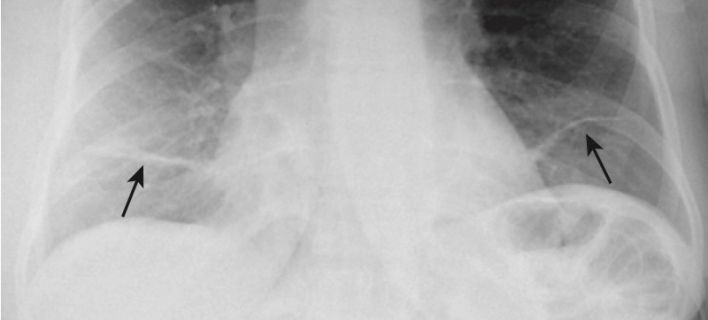

Xẹp phổi thùy dưới (Hình 12, A và Hình 12, B)

- Trên phim X quang thẳng:

- Cả thùy dưới bên phải và bên trái xẹp xuống tạo thành mật độ hình tam giác kéo dài từ đỉnh của rốn phổi đến đáy của nó ở phần trong của nửa cơ hoành bị ảnh hưởng.

- Có sự nâng lên của nửa cơ hoành ở bên bị ảnh hưởng.

- Tim có thể lệch về phía mất thể tích.

- Có sự dịch chuyển xuống dưới của rãnh liên thùy lớn (xem Hình 12, C).

- Trên phim X quang nghiêng:

- Có cả sự dịch chuyển xuống dưới và ra sau của rãnh liên thùy lớn cho đến khi thùy dưới bị xẹp hoàn toàn tạo thành mật độ hình tam giác nhỏ ở góc sườn hoành sau (xem Hình 12, B).

- Ở bệnh nhân nặng, xẹp phổi thường xảy ra nhất ở thùy dưới bên trái.

- Luôn kiểm tra nửa cơ hoành trái để chắc chắn rằng có thể quan sát được toàn bộ cơ hoành trái qua bóng tim vì xẹp phổi thùy dưới bên trái sẽ biểu hiện bằng sự biến mất (bóng bờ) của toàn bộ hoặc một phần của cơ hoành trái (xem Hình 12, A) .